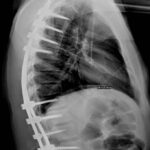

- Orientamento degli ultimi anni: solo artrodesi posteriore con sintesi peduncolare e osteotomie di Ponte

- A parte un recente lavoro di Koller (2013) che ripropone approccio combinato con viti peduncolari: 111 casi, 45% correzione e 4 mesi di busto ortopedico.

- Nostra strategia degli ultimi 10 anni, dopo la fase della chirurgia combinata: solo tempo posteriore, alta densità di viti peduncolari (oltre 90%) e osteotomie di Ponte.

- Inizialmente Montaggi Ibridi Unicini e Viti

- Successivamente montaggi Peduncolari